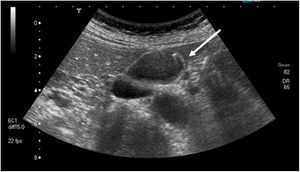

| Adenomyomatosis | Proliferation of epithelium with hypertrophy of the muscular layer with invaginations of hypertrophic mucosa through the thickened muscular layer (Rokitansky-Aschoff sinusoids); may be diffuse, segmental or focal. | Wall thickening with cystic spaces and comet-tail artifact (hyperechoic focus with posterior acoustic reverberation in the shape of an inverted triangle, with gradual decrease in echogenicity [Fig. 2]) |